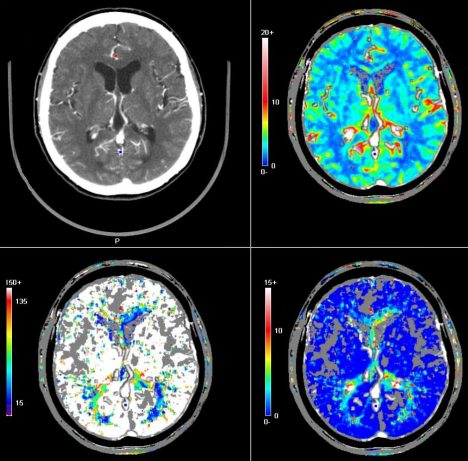

Mozkové buňky mohou měnit svou strukturu v průběhu celého našeho života a cvičení na to může mít výrazný vliv. Pomocí měření se totiž ukázalo, že tělesná aktivita dokáže vyvolat nárůst mozkové hmoty.